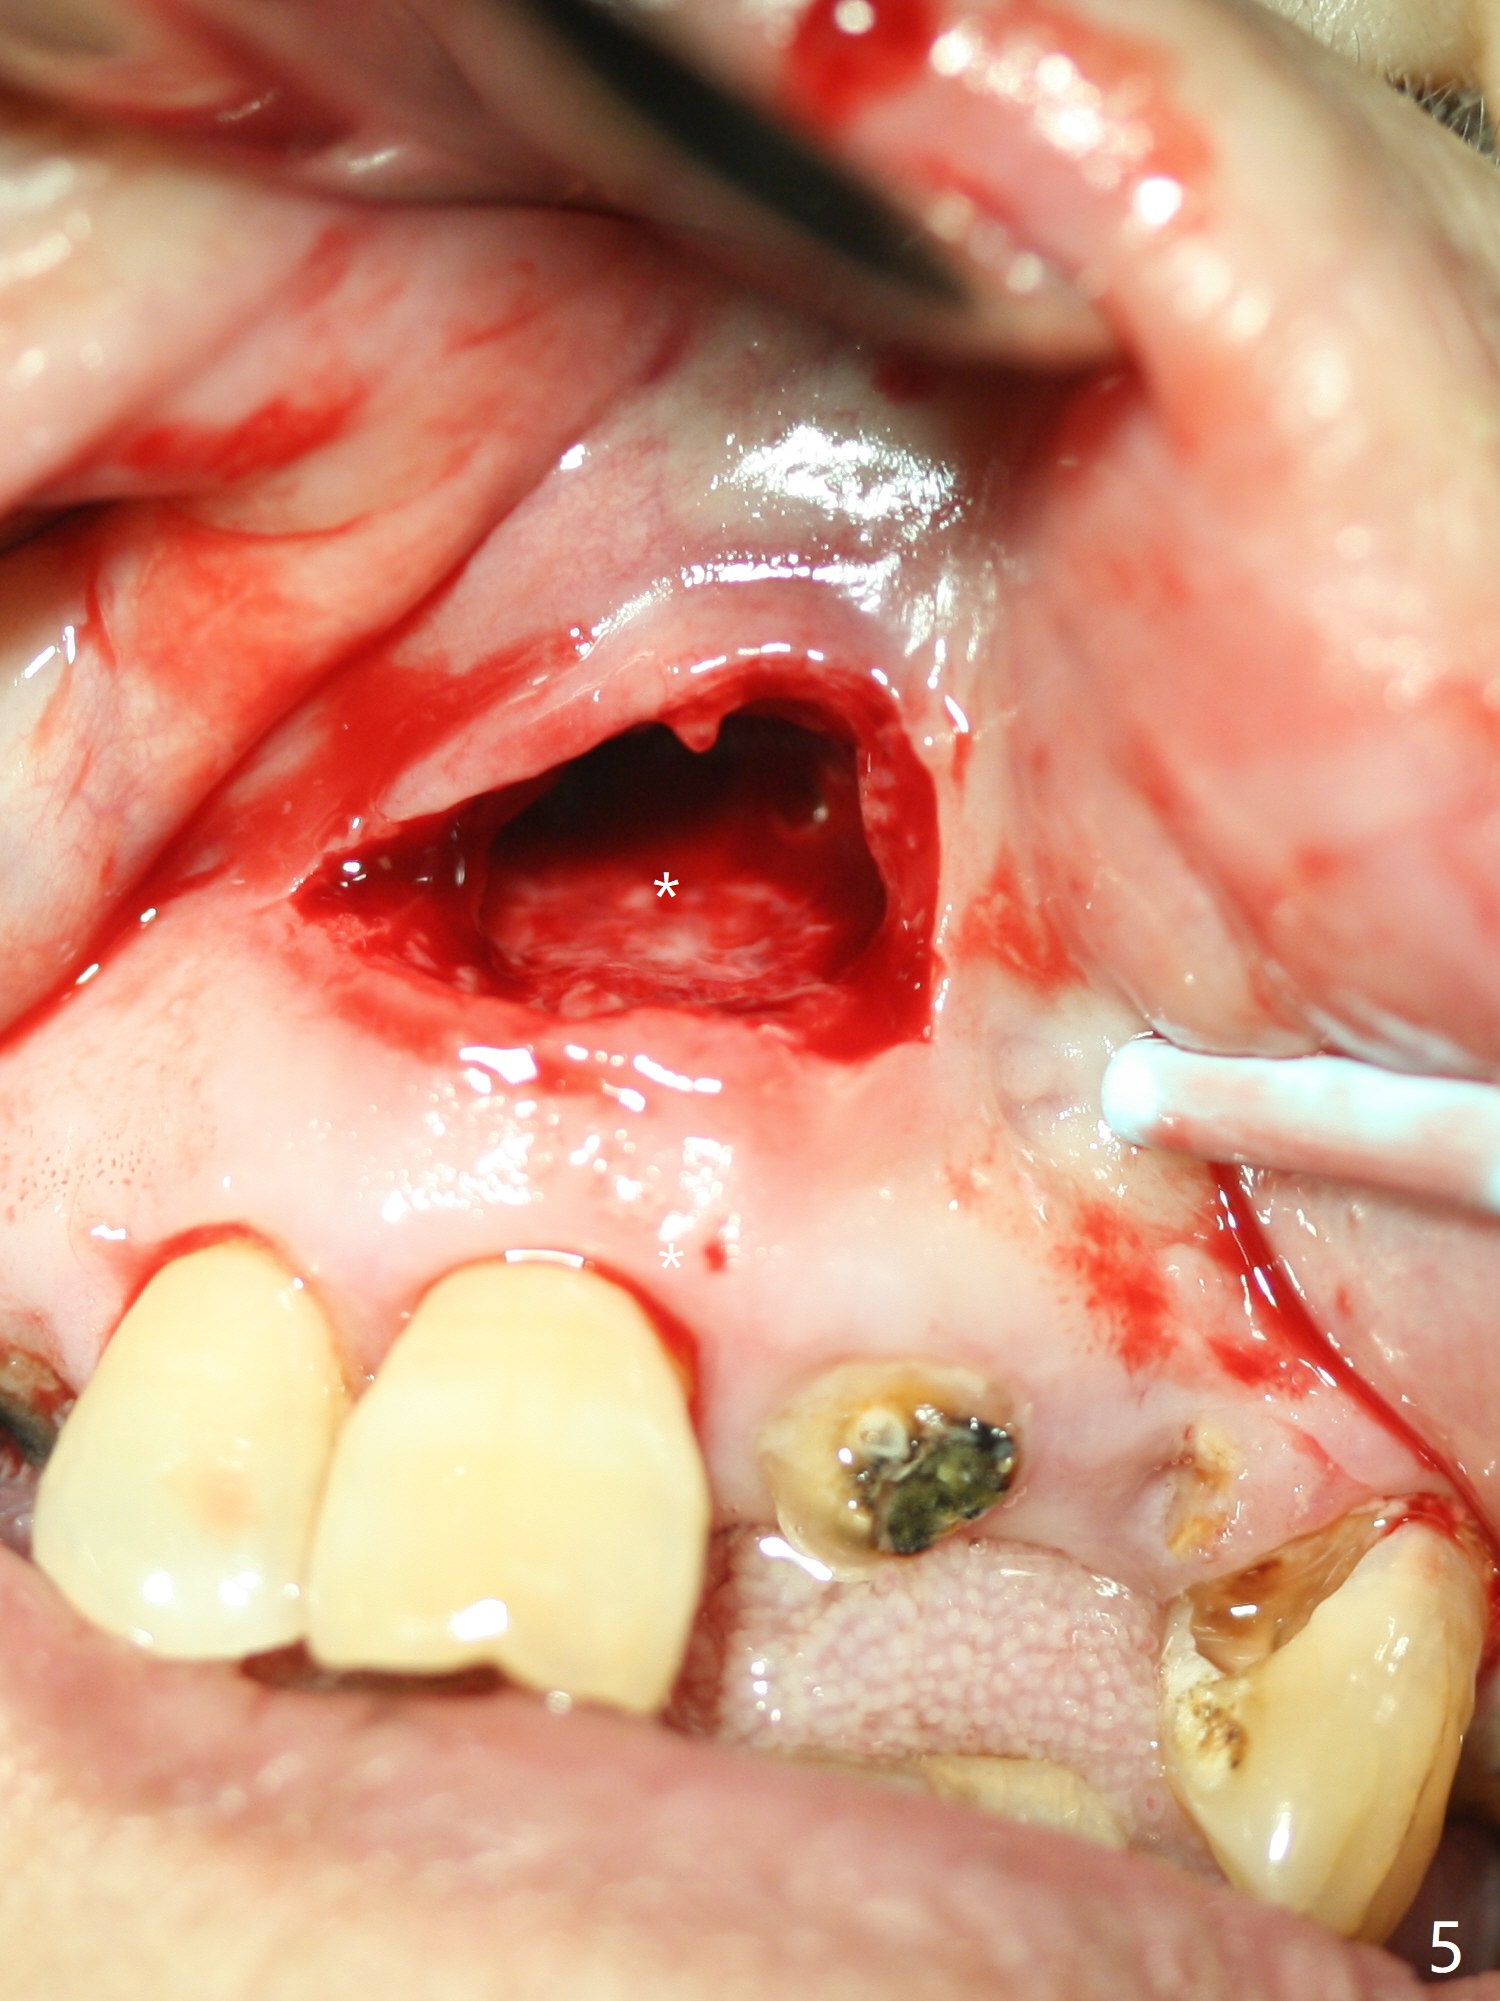

A 86-year-old woman with diabetes (under control with Insulin) and poor dentition (Fig.1) presented to clinic with an abscess apical to the tooth #8 (nonvital, Fig.2). CBCT (Fig.3) or PA (Fig.4) does not show radiolucency at #7 or 8. The incised abscess with purulent drained is superficial to the apparently intact periosteum (Fig.5 *). The patient is reluctant to have #7 and 8 extracted, since they are the only remaining functional dentition. The infection recurs 1.5 months later (Fig.6 * (^: previous incision)). With the periosteum elevated, fenetration over the apex of the tooth #7 (vital in pulpal test) is only seemingly significant finding (Fig.7). The abscess (Fig.8 A) is shown superficial to the periosteum (*). The infection is expected to relapse. What should be done otherwise? Full mouth extraction has been discussed.